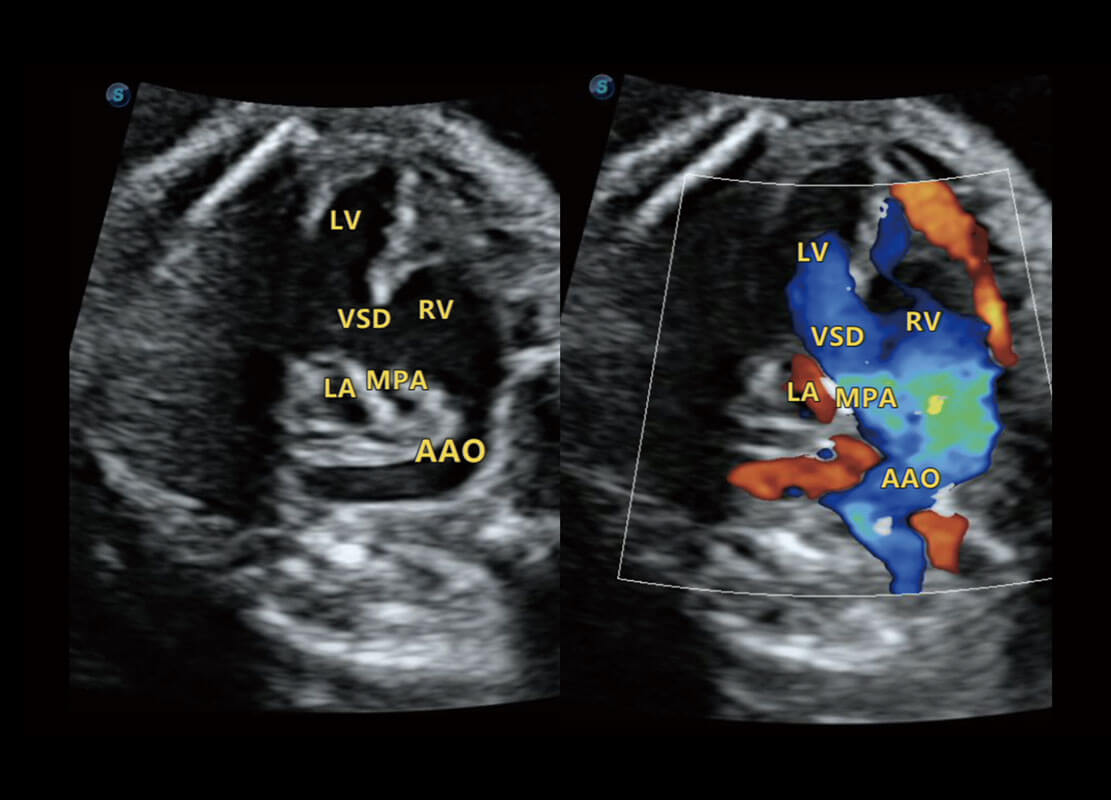

P60搭载一系列胎儿心脏成像技术,实现精细的胎儿心脏评估。

四腔切面

四腔心血流

右室双出口